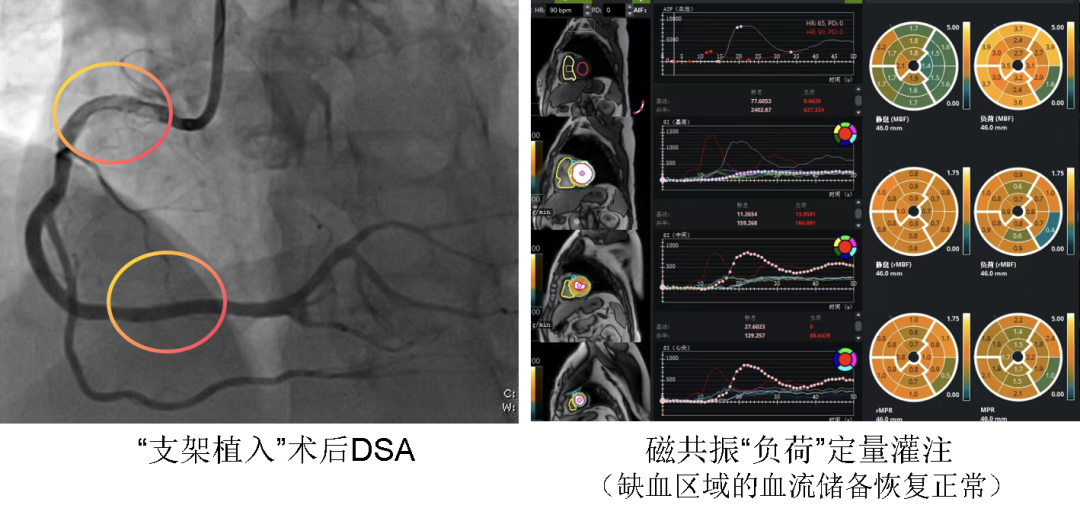

▲治療前 此次接受檢查的患者因間斷頭暈、心悸胸悶、暈厥來滄州市中心醫(yī)院就診。心臟彩超、動(dòng)態(tài)心電圖未見異常。冠脈造影提示右冠狀動(dòng)脈臨界病變,無法確定是否有心肌缺血的存在。經(jīng)心臟中心專家會(huì)診,決定采用這項(xiàng)國際領(lǐng)先技術(shù)進(jìn)行更深入的檢查。檢查過程中,專家團(tuán)隊(duì)?wèi){借豐富的經(jīng)驗(yàn)和高超的技術(shù),嚴(yán)格把控每一個(gè)環(huán)節(jié),確保檢查操作精準(zhǔn)無誤。檢查結(jié)果清晰、直觀地顯示了患者心肌缺血的具體部位和嚴(yán)重程度,不僅明確了診斷,更實(shí)現(xiàn)了對(duì)心肌缺血程度的全定量分析,為后續(xù)精準(zhǔn)治療提供了強(qiáng)有力的科學(xué)支撐。 ▲治療后 心臟中心專家憑借深厚的臨床經(jīng)驗(yàn),精準(zhǔn)把握適應(yīng)癥,為患者量身定制最優(yōu)檢查方案;磁共振成像科團(tuán)隊(duì)則依托先進(jìn)的磁共振設(shè)備和嫻熟的操作技術(shù),確保了圖像采集的高質(zhì)量與高精度。從檢查前的充分溝通、周密準(zhǔn)備,到檢查中的默契配合、無縫銜接,再到檢查后的聯(lián)合分析、精準(zhǔn)解讀,兩個(gè)團(tuán)隊(duì)以高度的專業(yè)素養(yǎng)和協(xié)作精神,為患者提供了全方位、一站式的優(yōu)質(zhì)診療服務(wù),充分彰顯了滄州市中心醫(yī)院強(qiáng)大的綜合實(shí)力。